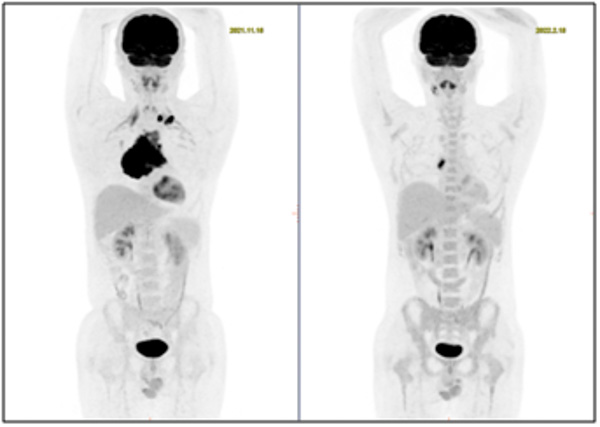

為確定治療方案,了解其他部位是否有淋巴瘤浸潤,進(jìn)行了PET-CT檢查,患者全身MIP圖一目了然!縱隔巨大腫塊淋巴瘤,左側(cè)鎖骨上窩淋巴結(jié)淋巴瘤浸潤。

治療4周期后,患者癥狀好轉(zhuǎn),再次到核醫(yī)學(xué)科行PET/CT顯像檢查,如圖所示。

治療后前上縱隔軟組織較前明顯縮小,仍有腫瘤活性組織存在;雙側(cè)鎖骨上窩、縱隔2組淋巴結(jié)均已吸收、滅活;右側(cè)胸膜及心包稍增厚。治療后病灶較前明顯縮小、減少,極大地緩解了患者相關(guān)臨床癥狀。